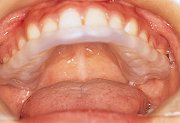

10

| スタビライゼーション型に移行したスプリントを口腔内に装着した。 |